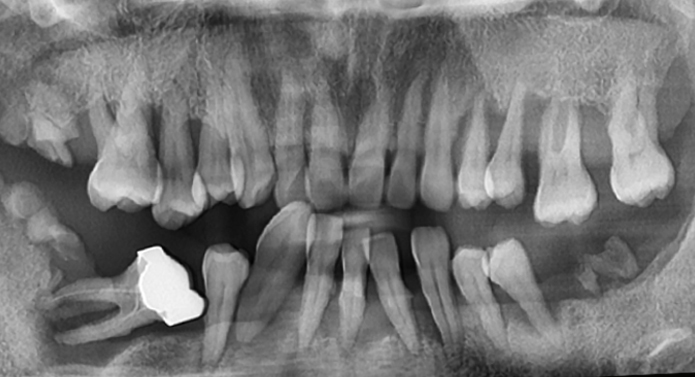

발치 → 뼈이식 → 임플란트 식립까지

하루에 가능한 시스템을 갖추고 있습니다.

가장 뼈가 잘 만들어질 수 있는 시점에 맞춘 치료가 가능합니다.

※ 단, 환자마다 잇몸뼈 상태가 다르기 때문에 정밀 진단 후 시술 가능 여부를 결정합니다.